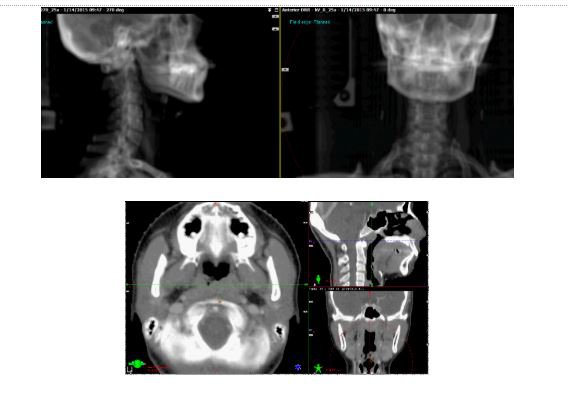

Bước 5: Xạ trị VMAT hàng ngày: Sử dụng bộ dụng cụ đặt tư thế và cố định bệnh nhân giống như lúc chụp CT mô phỏng. Trước khi chiếu xạ theo kế hoạch, tiến hành chụp xác minh (chụp x-quang hai chiều hàng ngày và chụp ba chiều CBCT 2 lần / một tuần) để kiểm tra các mốc xương và đánh giá sự chính xác của kỹ thuật.

Bệnh nhân đầu tiên ung thư vòm họng giai đoạn T3N2bM0